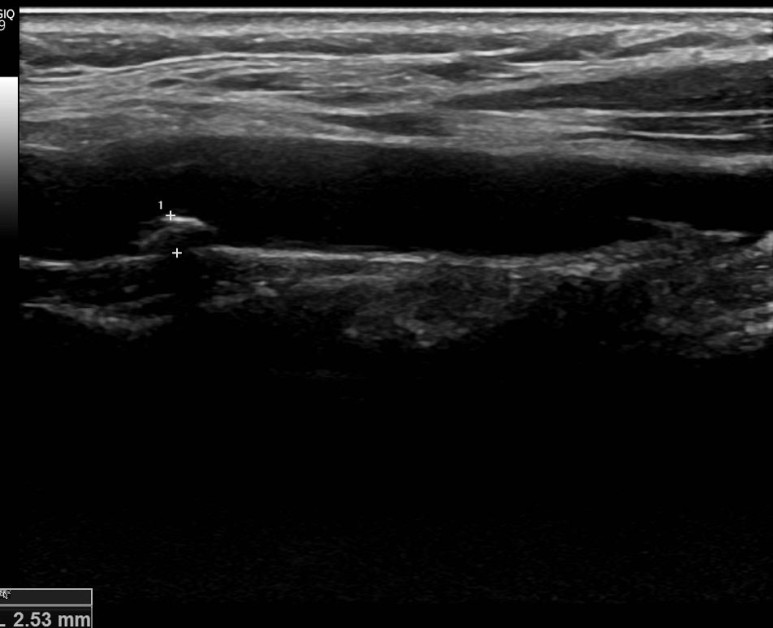

경동맥 초음파로 확인되는 동맥 경화반

뇌졸중의 원인이 될 수 있기 때문에 엄격한 고지혈증 관리가 필요합니다.